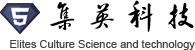

多人同步觀看

大屏同步投射

HoloLens項目體驗:

混合現實分享體驗會: